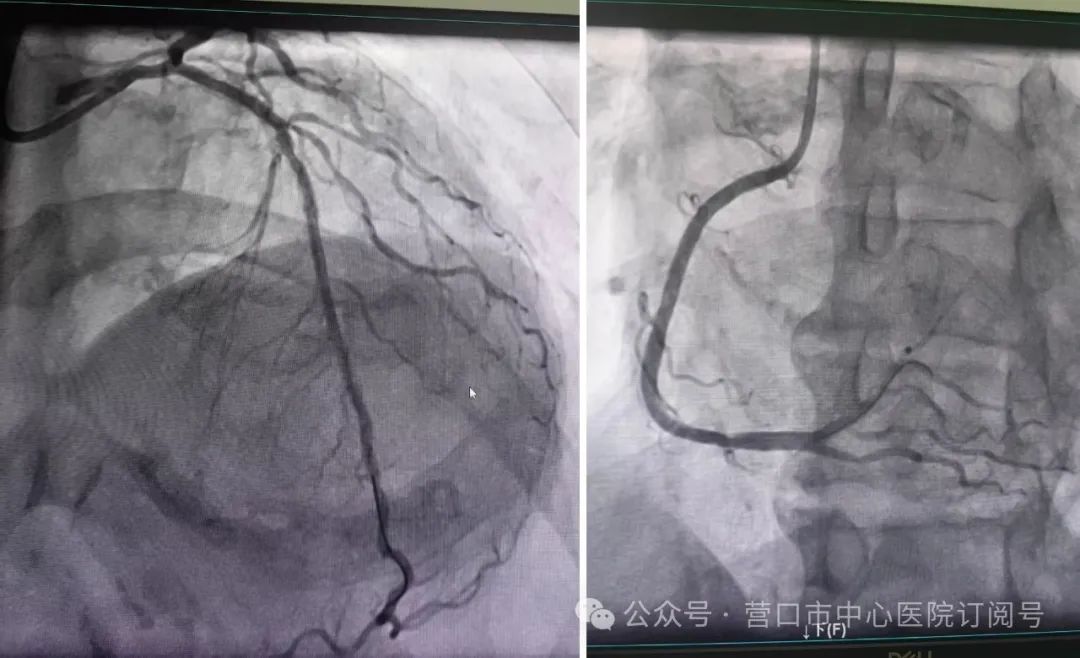

尽管手术指征明确,但患者刚经历直肠癌手术、肾功能代偿能力脆弱,冠脉介入治疗风险极高。经与家属充分沟通并获得全力支持后,2月10日,由曹兴阳、赵振梅医生组成的手术团队迎难而上。

术中发现患者冠状动脉严重狭窄,主刀医生曹兴阳凭借丰富经验,迅速完成动脉穿刺、球囊扩张及支架精准植入,全程仅用30分钟。术后患者胸痛症状即刻缓解,次日复查显示各项指标稳定,无需原计划的透析治疗。